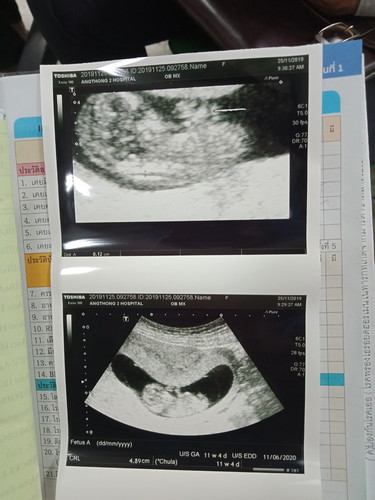

บ้านนี้11w 4d เห็นตัวน้องชัดมาก??

บ้านนี้ ไปซาวด์มา เมื่อศุกร์ที่แล้วค่ะ อายุครรภ์ตอนซาวด์ 10w 6d ❤️ ตอนนี้ อายุครรภ์ได้ 11w 3d แล้วค่ะ😍